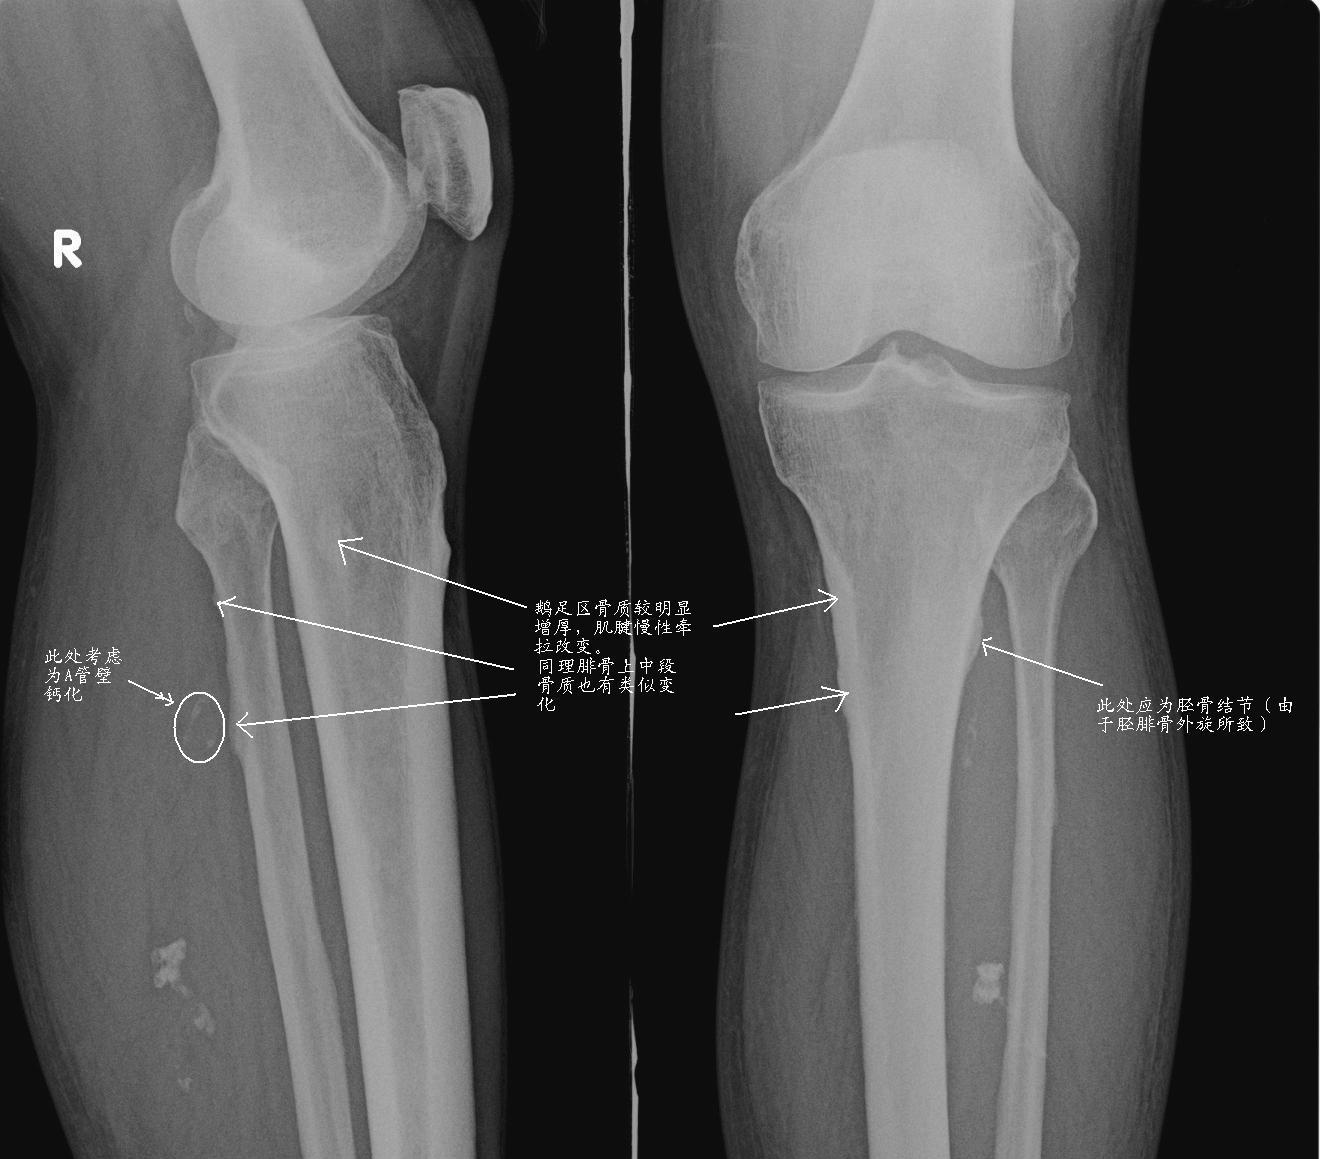

标题: X0965:胫腓骨片,

男 70y,腿部不适,前来就诊

考虑小腿软组织血管瘤或avm伴胫腓骨中上段局限性骨皮质增生,右膝关节退变。

1、右小腿软组织海绵状血管瘤。

2、右膝关节轻度退行性变。

1、软组织内钙化,多考虑血管源性,血管瘤或avm;2、右膝关节退变.

增生处应为肌腱附着点应该是正常的。

就是 血管钙化,稍上方可看到轨道样钙化。